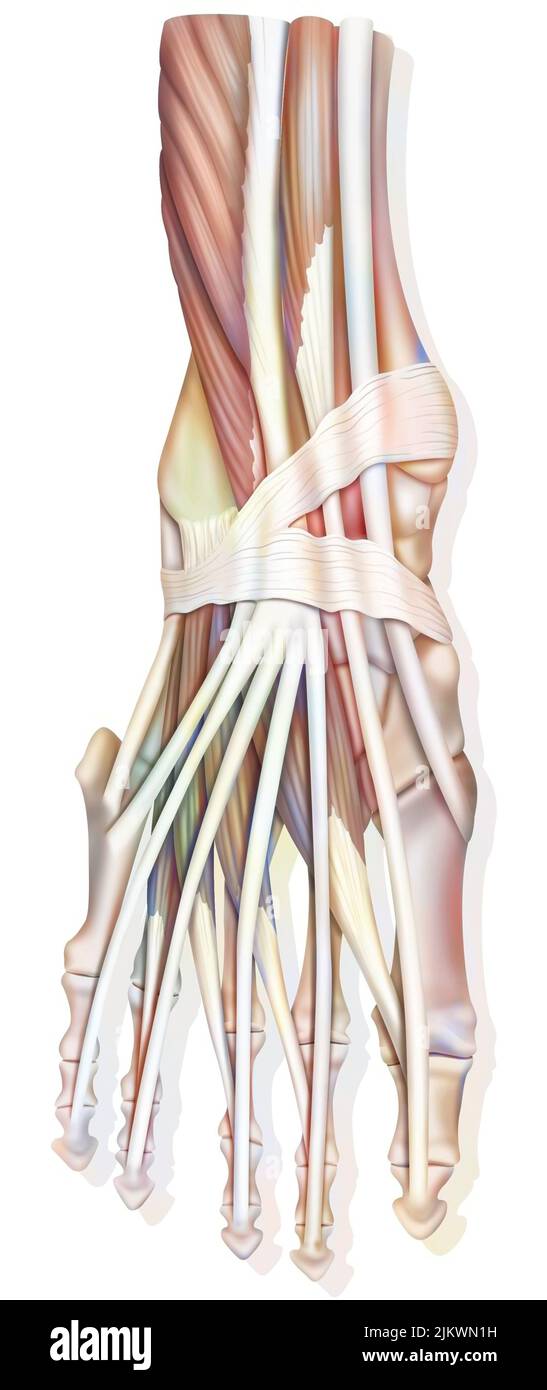

RF2ABM669–La médecine et les soins de l'illustre le tableau, les droits de l'anatomie du pied : Peau et tissus ectodermaux, os, muscles nerfs, vaisseaux sanguins

RFTCW7GT–L'articulation de la cheville, les tendons de la cheville anatomie pied eps vector illustration infographie 10